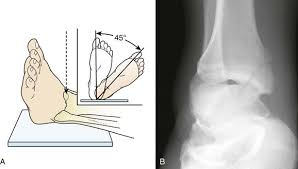

AP Medial Oblique ankle positioning/factors:

Foot position:

angle:

IR:

CR:

dorsiflex foot (toes up) so plantar surface is vertical to IR

internally rotate 45 degrees

lengthwise

Center midway between the malleoli.

AP Medial Oblique ankle structures best demonstrated:

Distal tibiofibular joint space open.

Lateral malleolus and talus articulation with little or no superimposition.

Medial malleolus partially superimposed